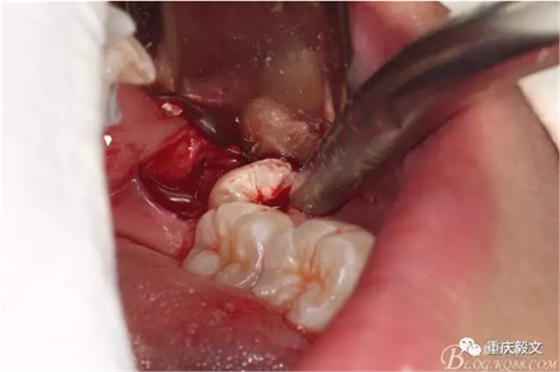

圖6.去骨要點(diǎn):去除骨組織阻力。視牙齒周?chē)亲枇Φ亩嗌俣ㄈス橇?,以暴露牙齒的外形高點(diǎn)線(xiàn)為宜。高速牙鉆去骨,以頰側(cè)去骨為主,遠(yuǎn)中可少量去骨。舌側(cè)禁止去骨。

圖7.縱分牙冠,分牙要點(diǎn):盡量多分牙、少去骨。根據(jù)牙根分布情況,來(lái)決定是縱分、斜分、還是橫分。